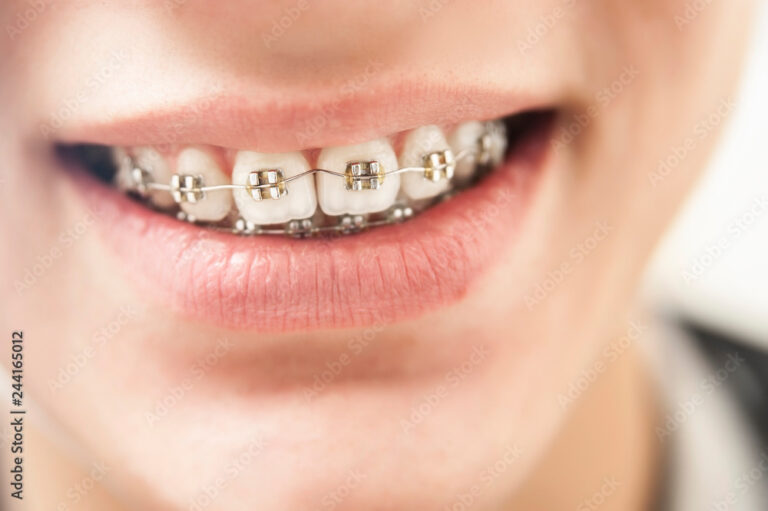

Selbstligierende Brackets

Bei dieser Art von Brackets wird der Bogen nicht mehr durch Drahtligaturen, sondern durch einen speziellen Mechanismus im Bracket selbst fixiert. Die daraus resultierende geringere Friktion (Reibung) bedingt kürzere Behandlungszeiten und eine perfekte Verzahnung. In sehr vielen Fällen beträgt die Bracketstragezeit dadurch nicht länger als ein Jahr.